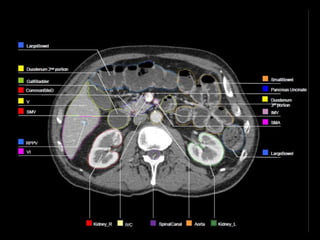

ROI Delineation:Ao and PV

 Aorta(Ao) extending from top of the upper most PV,CA or

SMA slice to the bottom of L2 or L3.

 Portal vein(PV) is contoured from the bifurcation of the PV .

The PV bifurcation can be extrahepatic or almost

intrahepatic.

(portion of portal vein running anterior and medial to IVC

and stop prior to confluence of SMV or splenic vein).

ROI Delineation:CA and SMA

 Celiac artery (CA): The most proximal 1.0-1.5 cm of the

CA and should include up to the first branching.

 Superior mesenteric artery (SMA): The most proximal

2.5-3.0 cm of SMA.

ROI Expansions

 Pancreaticojejunostomy, portal vein, superior mesenteric

artery and celiac artery are expanded by 0.5-1 cm.

 Aorta ROI is given asymmetric expansion; 2.5-3 cm

towards right , 1cm towards left, 0.2 cm posteriorly and 2

-2.5 cm anteriorly.

 The CTV is then created by merging the ROI expansions .

 The posterior margin should follow the contour of the

anterior aspect of the vertebral body without including

more than 0.5 cm of the anterior vertebral body anterior

edge.